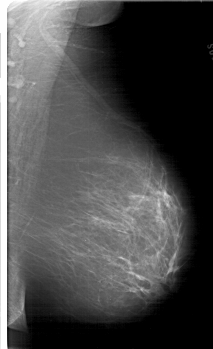

A_1719_1.LEFT_CC

LEFT_CC LINES 6781 PIXELS_PER_LINE 3811 BITS_PER_PIXEL 12 RESOLUTION 43.5 OVERLAY

FILE: A_1719_1.LEFT_CC.OVERLAY

TOTAL_ABNORMALITIES 1

ABNORMALITY 1

LESION_TYPE MASS SHAPE LOBULATED MARGINS MICROLOBULATED

ASSESSMENT 4

SUBTLETY 3

PATHOLOGY BENIGN

TOTAL_OUTLINES 1

BOUNDARY